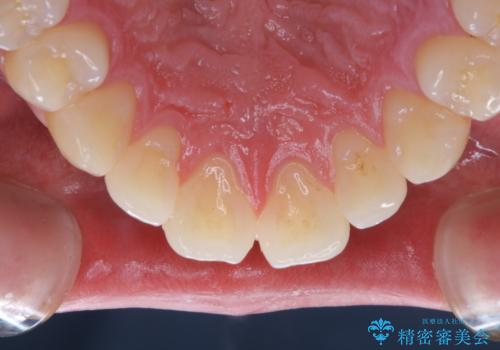

親知らずを抜いて1週間後にPMTC 歯のクリーニング

- 親知らずの抜歯後の約1週間後に抜糸(縫った部分の糸とり)で来院されました。その際、抜歯後は傷口が怖くて歯磨きが上手くできず、汚れや口臭が気になるためクリーニングも希望されました。

抜歯後は多少出血したり、違和感や痛みを感じたりすることがあります。そのため親知らずを抜いたり、外科的な処置をするといつも通りの歯磨きがしづらくなります。また、傷口の周りが心配で、歯ブラシをするのが怖くなるものです。抜歯後落ち着いたら、歯科医院にて専門の機械を使用しクリーニングをすることがおすすめです。抜歯前や後にPMTCを行うことで、お口の中の健康維持につながり、その後の感染・腫れ・口臭予防などになります。